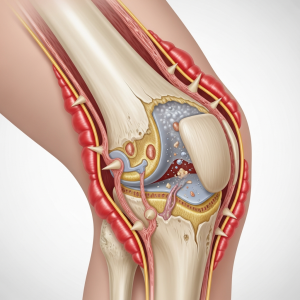

وقتی بدن در حالت خواب قرار دارد، جریان خون و حرکات مفصل کاهش مییابد. این شرایط باعث میشود مایع مفصلی که وظیفه لغزندگی و تغذیه غضروف را دارد، کمتر در مفصل گردش کند. نتیجه این میشود که هنگام بیدار شدن، مفصل خشکتر، سفتتر و کمتر روان است.

در افراد سالم این فرایند خفیف و طبیعی است. اما اگر غضروف آسیب دیده یا التهاب وجود داشته باشد، خشکی طولانیتر و شدیدتر میشود.

آرتروز نتیجه نازک شدن غضروف، التهاب بافتهای اطراف مفصل و تغییر کیفیت مایع مفصلی است.

وقتی غضروف شروع به تخریب میکند:

حساسیت مفصل به بیحرکتی افزایش مییابد

مایع مفصلی غلیظتر میشود

لایههای مفصل اصطکاک بیشتری دارند

حرکت اولیه مفصل سختتر میشود

در نتیجه هنگام بیدار شدن از خواب، مفصل نیاز دارد اول “گرم” شود تا روان شود. این دقیقاً همان خشکی صبحگاهی است.